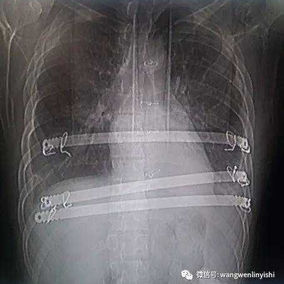

Preoperative Examination

The chest wall exhibits a large area of prominent and bilaterally symmetrical protrusion, predominantly in the upper half. There are also mild depressions on both sides of the lower half of the chest wall.

First, two 3 cm incisions were made on each side of the chest wall, followed by a 2 cm incision along the old surgical scar in the middle of the chest wall. Two bars were then placed on the protruding bone structures of the chest wall to perform the Wenlin procedure. Since the anterior chest wall is a rigid whole, correcting and pressing down the protrusion in the upper chest often causes a secondary depression below it. To address this, a third bar was inserted into the chest cavity to perform the Wung procedure, thereby elevating the depressed areas. Ultimately, the patient’s chest wall deformity was corrected, and the surgery achieved a satisfactory outcome.